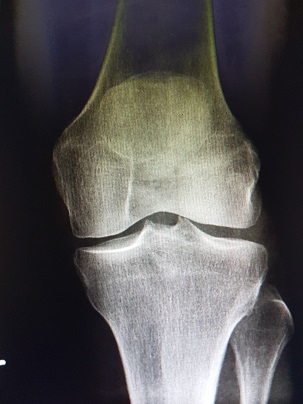

Seit 1975 bin ich operativ tätig und erwarb über die Jahre eine Spezialisierung auf dem Gebiet der athroskopischen minimal-invasiven Chirurgie (Instruktor der AGA seit 1986). 1986 gründete ich meine Praxis in der Clausewitzstraße 4 in Berlin Charlottenburg, in der ich seit diesem Jahr tätig bin. Parallel hierzu operierte ich zuletzt ambulant im OP-Zentrum Spichernstraße.